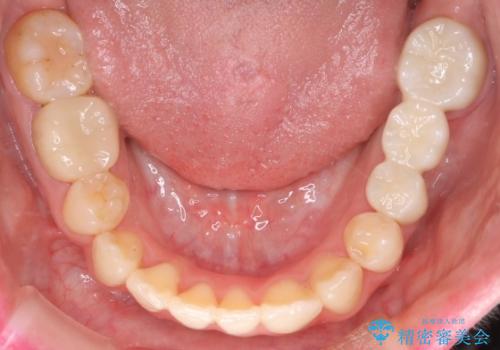

八重歯のワイヤーによる抜歯矯正 矯正治療と並行してセラミック治療も

今回の場合も、ブリッジを除去して矯正後にセラミックブリッジを装着しました。